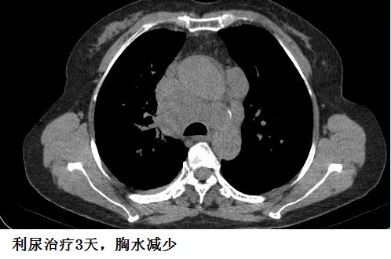

下面这个患者,纵膈淋巴结肿大、融合,心包积液,胸腔积液,一看就是晚期肺癌。后来,纤支镜也确实查到癌细胞。

这个胸水,不好抽,但也不难抽。癌性胸水,不抗癌治疗,不引流,一般不会自行吸收。我带同学去抽胸水,为了安全起见,我事先还是用B超探查了一下胸水,我瞬间就懵了:居然只有极少量的胸水。

复查CT,“癌性胸水”果然无缘无故减少了。

这个患者的胸水,应该是心包积液导致静脉回流受阻,体循环淤血引起的。利尿治疗后,胸水减少。